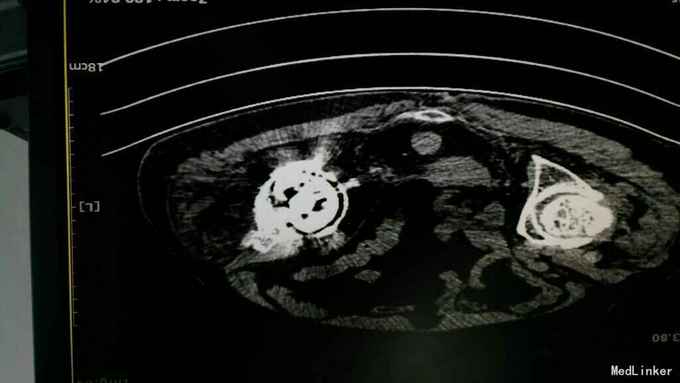

主诉:左髋关节置换术后疼痛活动受限3年 病史:3年前患者因左股骨颈骨折在当地县医院就诊,诊断明确后行全髋关节置换术,术前正常出院。出院后即感左髋关节疼痛不适,活动疼痛加重,休息缓解,疼痛位于腹股沟明显。反复于当地医院及成都等医院就诊,诊断不明确,考虑有金属过敏可能。4天前患者疼痛加重,活动进一步受限,无关节红肿,无肿胀,无畏寒发热,无其他关节疼痛。为进一步治疗收入我科。 患病以来。精神食欲可,体力下降。

查体:轮椅推入,左髋关节后外侧见10cm手术切口瘢痕,双侧腹股沟压痛,双侧大转子叩痛,双髋关节活动受限,4字实验(+),双下肢肌力3级。左乱关节屈曲90度,旋转不能。左下肢纵向叩痛(+)。 辅助检查:彩超示脂肪肝。x线腰椎骨质疏松,压缩性骨折。ESR 38,CRP 12。 影像学如下:

诊断:左髋关节置换术后假体松动; 右侧股骨头缺血坏死; 重度骨质疏松症 高血压病 压缩性骨折 治疗:左髋关节翻修术。(植骨、钛网骨水泥杯,骨水泥柄或翻修长柄MP(Link))

术中见骨质疏松明显,股骨劈裂,捆扎带固定。 术后股骨是否好愈合?